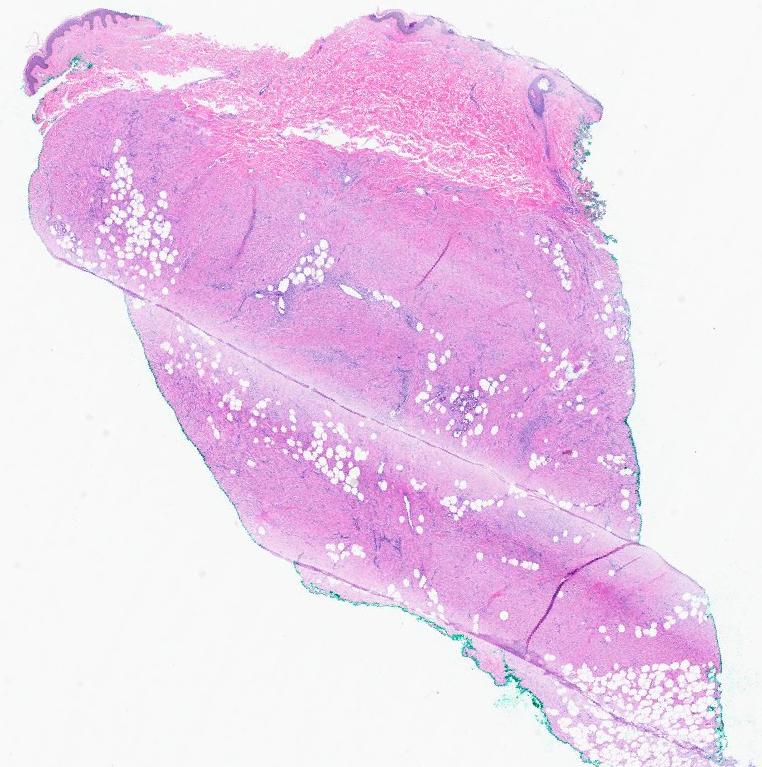

#dermpath 70s year old female cheek lesion, clinical SCC. Clearly not. Pericytic tumor. what is the best call for it? @redsnapperpath @et565 @david_terrano @Dr_Jukic @DrGeeONE @kis_lorand @gonzadetoro @SGottesmanMD @HoustonArsenal